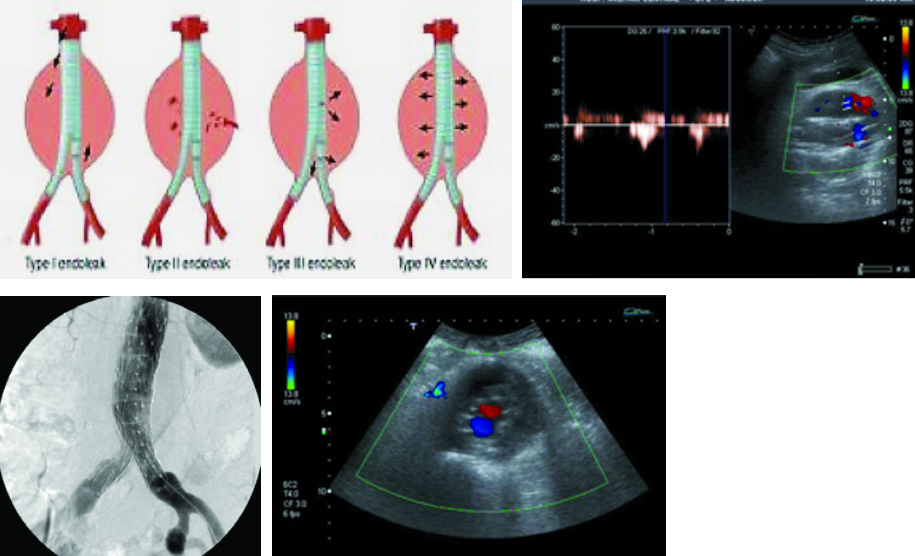

Los controles imagenológicos post tratamiento son de importancia, y es indispensable la caracterización morfológica del aneurisma y la endoprótesis. De esta manera, debemos medir el tamaño del aneurisma, la presencia de flujo dentro de la prótesis, la ausencia de flujo peri protésico, la presencia de flujo en arterias renales y la adecuada velocidad de flujo en las arterias ilíacas (Fig. 41, 42 y 43).

Las complicaciones luego de instaurado el tratamiento pueden ser el crecimiento del aneurisma, embolias, desgarros del tejido protésico, infección o migración del injerto, fractura de los ganchos, separación de una rama o la presencia de endofugas. Estas se clasifican en cinco tipos(24) (Tabla 6).

- Tipo I: hay presencia de flujo sanguíneo fuera del lumen protésico adyacente al sitio de anclaje. En Ia, proximal en la arteria y en Ib, distal en la arteria. Se produce por una mala fijación en el sitio de anclaje entre la prótesis y la pared arterial. Son más frecuentes en las endoprótesis torácicas, y se deben tratar en forma urgente (Fig. 44 y Fig. 45).

- Tipo II: son las más frecuentes. Se producen por flujo retrogrado desde una rama arterial excluida por la endoprótesis, y es común la afectación de la arteria mesentérica inferior y las arterias lumbares. La fase tardía de la angiotomografía identifica la presencia de contraste en la periferia del saco aneurismático que no contacta con la endoprotesis (Fig. 46).